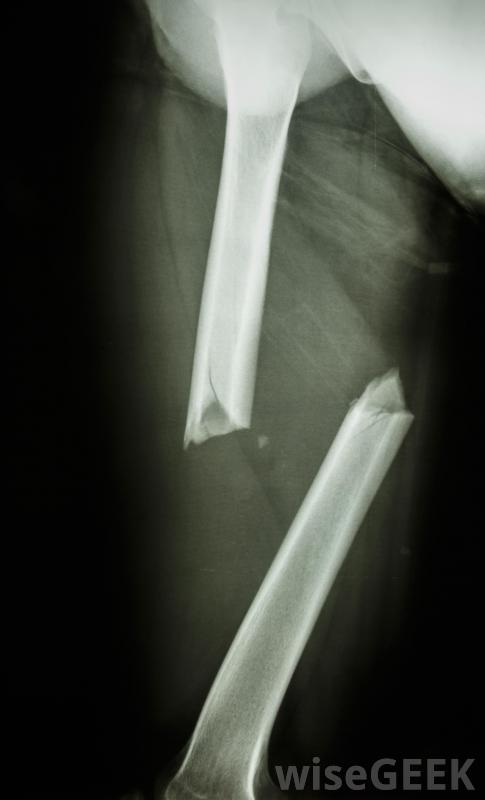

什么是骨骺骨折(Epiphyseal Fracture)?

生長中的兒童長骨一端的骨折,包括其生長板,稱為骨骺骨折。未成熟長骨每端附近的軟骨盤使骨骼生長。這些生長組織區域稱為骺板,在兒童成熟至成年時變硬。骨骼中的生長板是骨骼結構最薄弱的部位,容易受傷,稱為骨折。這種骨折有時被稱為Salter骨折或Salter Harris骨折。壓縮性骨折通常需要骨骺外科治療和重建手術。骨的骨干稱為骨干,而兩端的圓形部分稱為骨骺。在這兩個區域之間有一個骨的擴張部分每端稱為干骺端。骺板位于長骨兩端的骺和干骺端之間。根據骨折部位的不同,骺骨折可分為五種或六種骨折類型之一骨骺骨折有五種或六種類型,根據骨折部位的不同,Ⅰ型骨折包括骨骺與干骺端完全分離骨折穿過骨骺板,骨骺板與骨骺相連。這種骨折通常需要固定,如果有明顯移位,有時需要重新定位骨塊。假設骺板的血液供應沒有中斷,長骨兩端的圓形部分稱為骨骺穿過生長板和干骺端但不累及骨骺的骨折被歸類為II型骨折。這是最常見的骨骺骨折類型。通過固定和休息,以及在必要時重新定位骨或生長板,骨折通常會隨著時間的推移愈合和加強兒童在被診斷為骨骺骨折之前,可能需要接受多次X光檢查。一種更罕見的骨折骨骺和生長板與干骺端分離的部分屬于III型骨骺骨折。青少年最容易遭受這種損傷。它通常發生在脛骨下端,脛骨是小腿的長骨之一。這種類型的骨折有時需要手術治療骨折盡管如此,如果骨骺分離部分的血液供應得以維持,骨骼正常生長的機會仍然很大。骨骼中的生長板是骨骼結構中最薄弱的部分IV型骨折貫穿骨骺、骺板和干骺端。對于這種非常嚴重的損傷,通常需要進行手術,以使骨塊完全對齊。如果在手術過程中不能保持良好的對齊恢復期,骨正常生長的前景不佳。骨骺骨折常見于脛骨下端骨骺板壓縮性骨折是罕見的,通常包括骨頭末端和生長板的壓碎,這種損傷屬于V型骨骺骨折,預后差,最典型的是導致生長發育不全,很難被發現,而且通常在正常生長障礙變得明顯之前仍然無法被診斷出來。這類骨折通常需要外科治療,而且通常還需要后期的矯正手術兒童的骨骼可能會出現一些醫學問題有些分類系統增加了一個Ⅵ型骨骺骨折,其中部分骨骺、骺板和干骺端完全缺失。這類骨折通常是外傷造成的,如重型機械事故、槍傷等。與V型骨折一樣,這些骨折通常需要手術治療和隨后的重建手術。它們通常也會導致生長發育遲緩。對一個沒有受傷的可比區域進行第二次X光檢查,如一個人和另一個肘部,可能是在診斷骨骺骨折的過程中被要求的。骨骺骨折的診斷并不總是直接的。在對病人進行檢查后,醫生通常要求對受累部位進行X光檢查。第二次為了比較,也可以訂購一個類似的未受傷區域的X光片,例如另一個肘部。如果這些X光片的發現不充分,可以要求進一步成像,如計算機輔助斷層掃描或磁共振成像骨骺骨折發生在兒童長骨的末端,并隨著時間的推移而愈合。